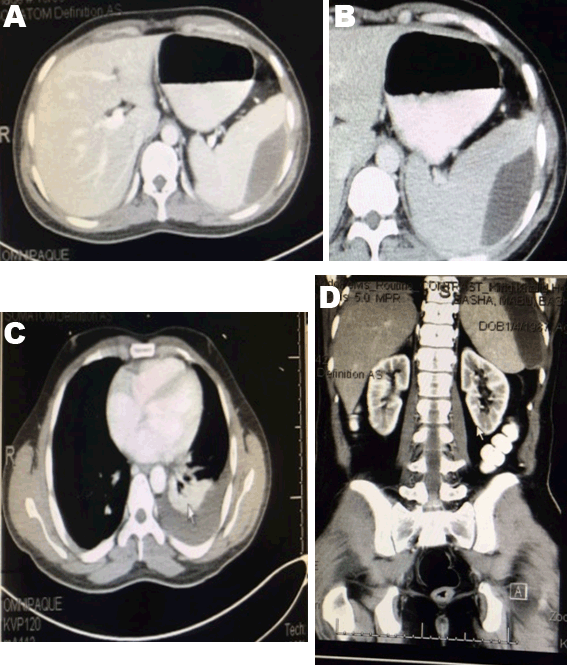

A 30-year-old Indian male presented to our emergency room, a RTA victim, with lower abdominal pain. Resuscitation started according to ATLS protocol and examination was unremarkable except for suprapubic tenderness, tear of glans penis and right side of scrotum. Laboratory workup showed raised renal functions. Focused assessment with sonography for trauma (FAST) showed mild free intraperitoneal fluid. X-rays showed bilateral lung contusions and pelvic fracture. Computed tomography (CT) scan without contrast was not done due to raised serum creatinine of 145 µmol/L and urea of 11 mmol urea per liter. Scrotal ultrasonography and Doppler were normal. Repeated hemoglobin was 8 g/dl, then ultrasound showed increased intra-abdominal fluid. He was prepared for laparotomy. 1.2 liters of free blood, normal solid organs except for 1 cm lateral capsular splenic tear with minimal bleeding were found. Splenic salvage was done with cautery and 2 pieces of pieces of local hemostats (Surgicel™). Resection anastomosis of 30 cm of ilium was done for transverse large mesenteric tear of the distal ileum. Wash with saline then, the abdomen was closed over drains. On the next day, he developed hematuria. Computed tomography (CT) scan with contrast showed normal solid organs. On day-10, blood workup and ultrasound were unremarkable. Drains removed and antibiotics were discontinued. He remained for wound infection care. On day-18, he had fever and subcostal pain. Clinically, he had mild left subcostal tenderness with no masses. Ultrasonography and abdominal contrast enhanced CT scan showed a subcapsular 12x6.5x3.6 cm splenic hematoma with no free intraperitoneal fluid, left pleural effusion and basal lung consolidation (Figure 1). Conservative treatment continued for 10 days and till complaining of pain. Follow-up CT scan showed no improvement. He was offered ultrasound-guided percutaneous drainage or splenectomy as alternative in case of failure of drain. 40 ml of turbid blood was aspirated and sent for culture. A 16 F pigtail catheter was left inside the cavity. Post procedure chest X-ray showed a left hydropneumothorax that improved later (Figure 2). The culture of the aspirate was negative. He did well. Regular catheter care with flushing with 5 ml saline. On day-9, the drainage was reduced to 5 ml and serous. The catheter drainage stopped after three days. Ultrasonography showed obliteration of the cavity. The catheter was removed. He was discharged in a good condition and came for outpatient department follow-up three weeks later and was free of complaints. He did not agree to do follow-up CT scan as he had it three times during the course of treatment. CBC and ultrasonography were normal. He has regular follow-up.

Figure 2: (A) The catheter showed altered aspirated blood, (B) A mild a left hydro-pneumothorax, percutaneous catheter drain and contrast in the colon from previous computed tomography scan are shown in the post-procedure chest X-ray, and (C) A discharge chest X-ray.